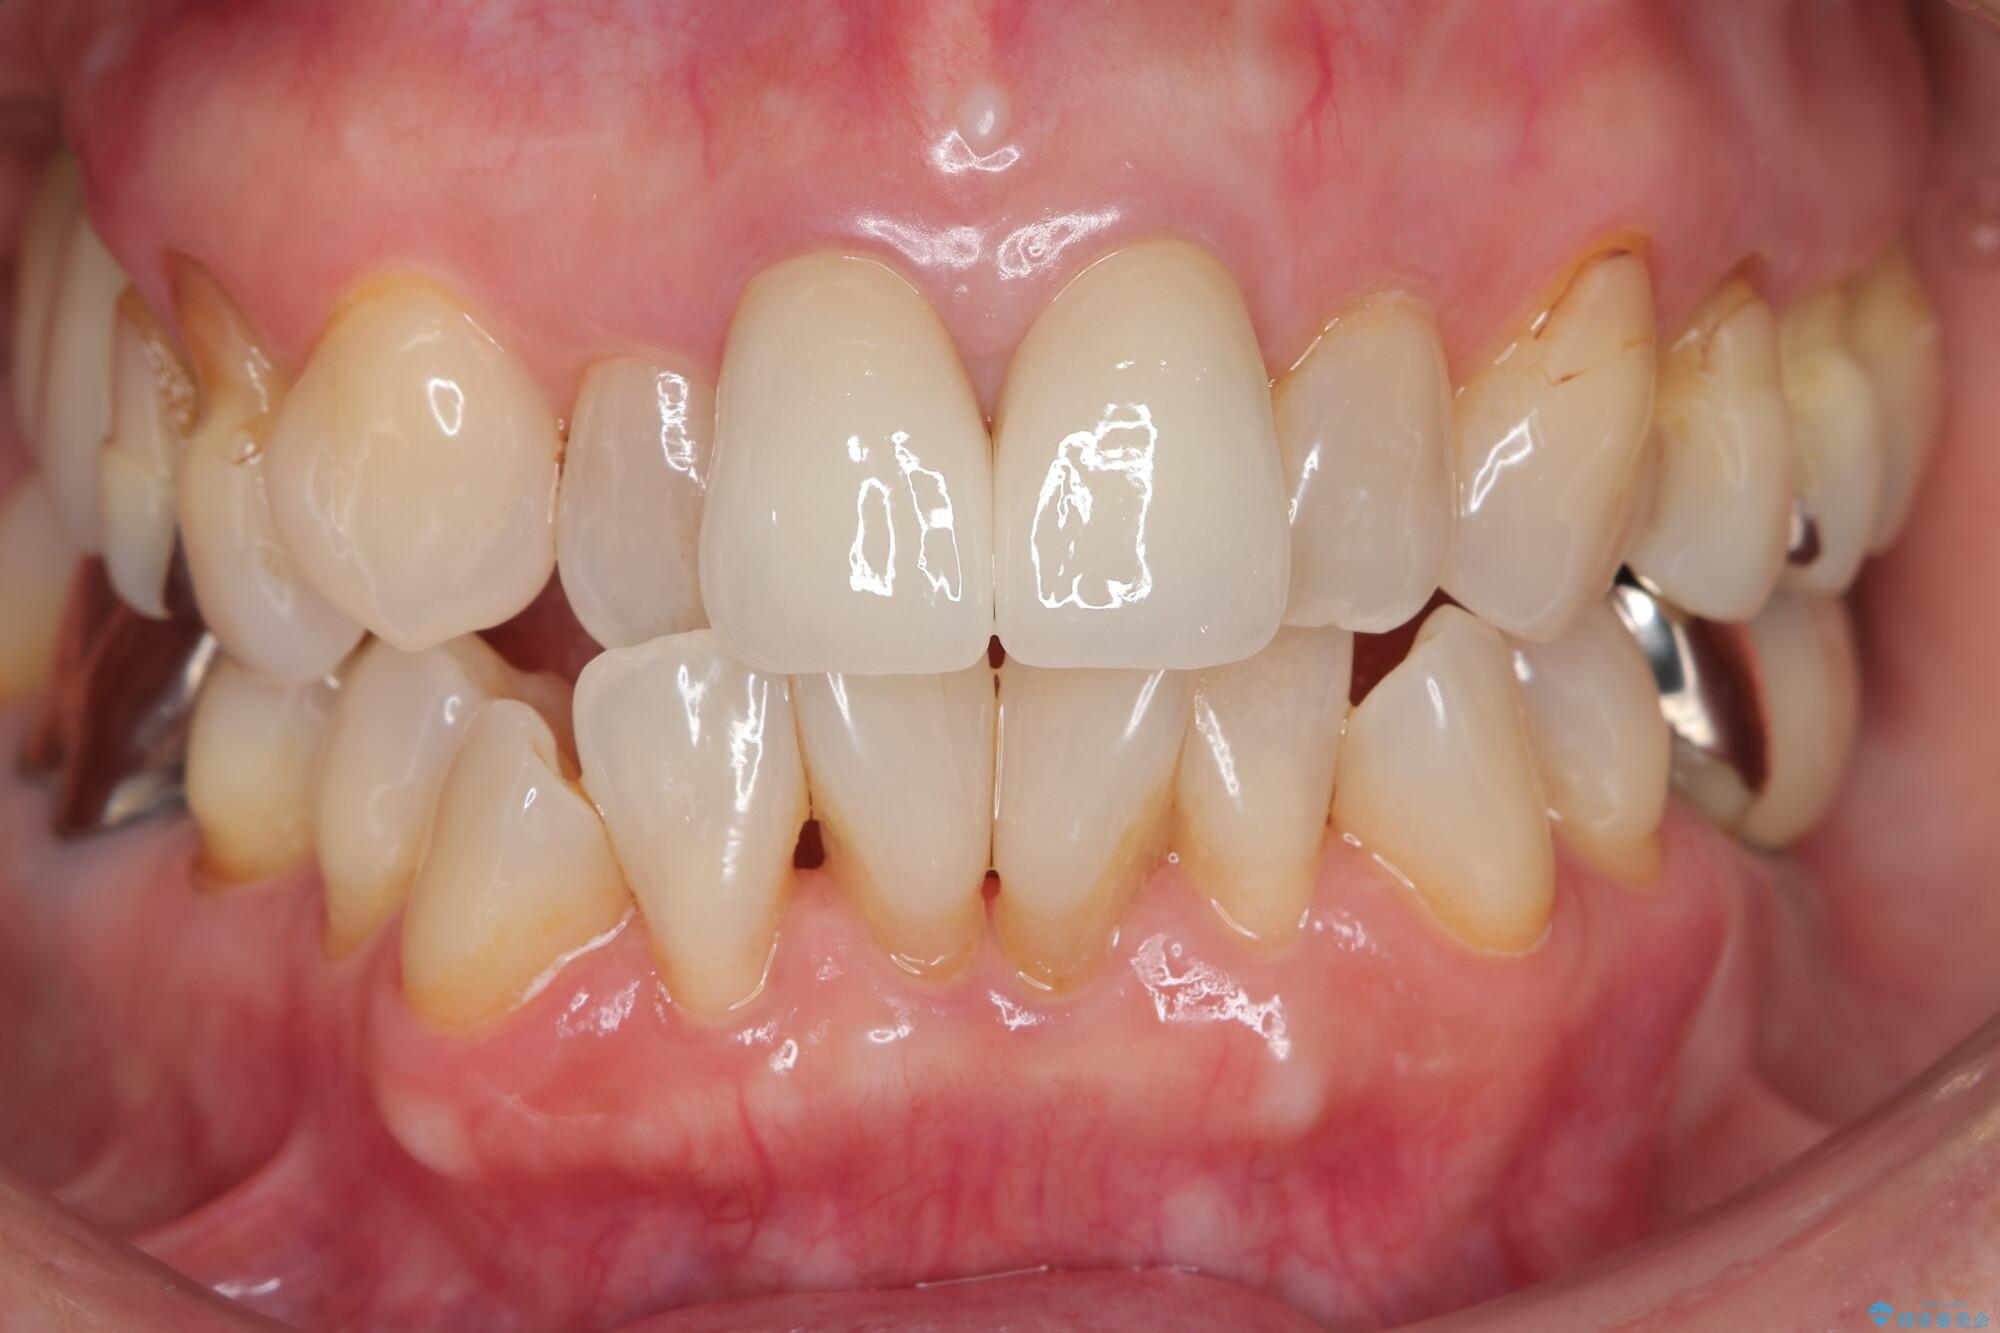

黒ずみもなくなり、自然な色味で大変ご満足いただけました。

審美性に優れるジルコニアクラウンによる治療を計画します。